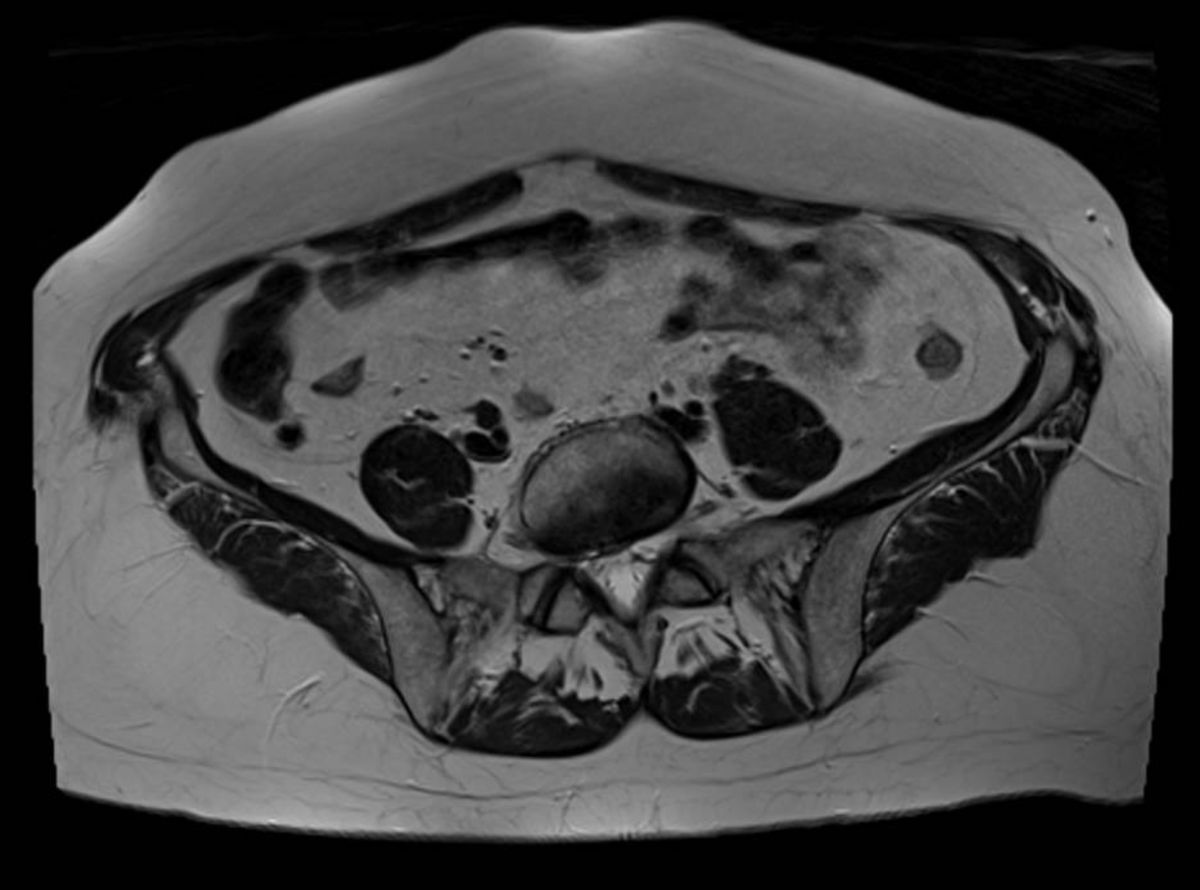

Consent ✅

F 60s

Years of diffuse R gluteal, hip & thigh pain, constant, stairs & sitting aggravates

Seen by orthopaedics to evaluate hip & knee (previous patellectomy this side) - referred to me as unable to identify pain driver & MRI scans 'normal'

MRI pelvis - hip joints & lateral soft tissues are fine

Clear suspect for her pain though, even on first glance - what do you see?

Always check the images yourself - and bear in mind can pick up helpful pathology on non-dedicated series so worth scrutinising it all